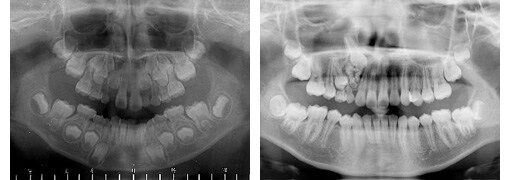

親知らずまで32本全部そろっているように見えるんだが、

一本は乳歯のままなのか。写真左上の糸切り歯がそうかな?。

15: <丶`∀´>(´・ω・`)(`ハ´ )さん@\(^o^)/ 2016/07/16(土) 23:12:57.25 ID:vZvg4aSw.net

ここまで眼窩に近いのは初めて見た

逆生で上顎内にあるのはよく見るけど

右上Cが残っていて、右上3番が逆生しとるんだな

てか、この人、左上3と4の間にも何かない?